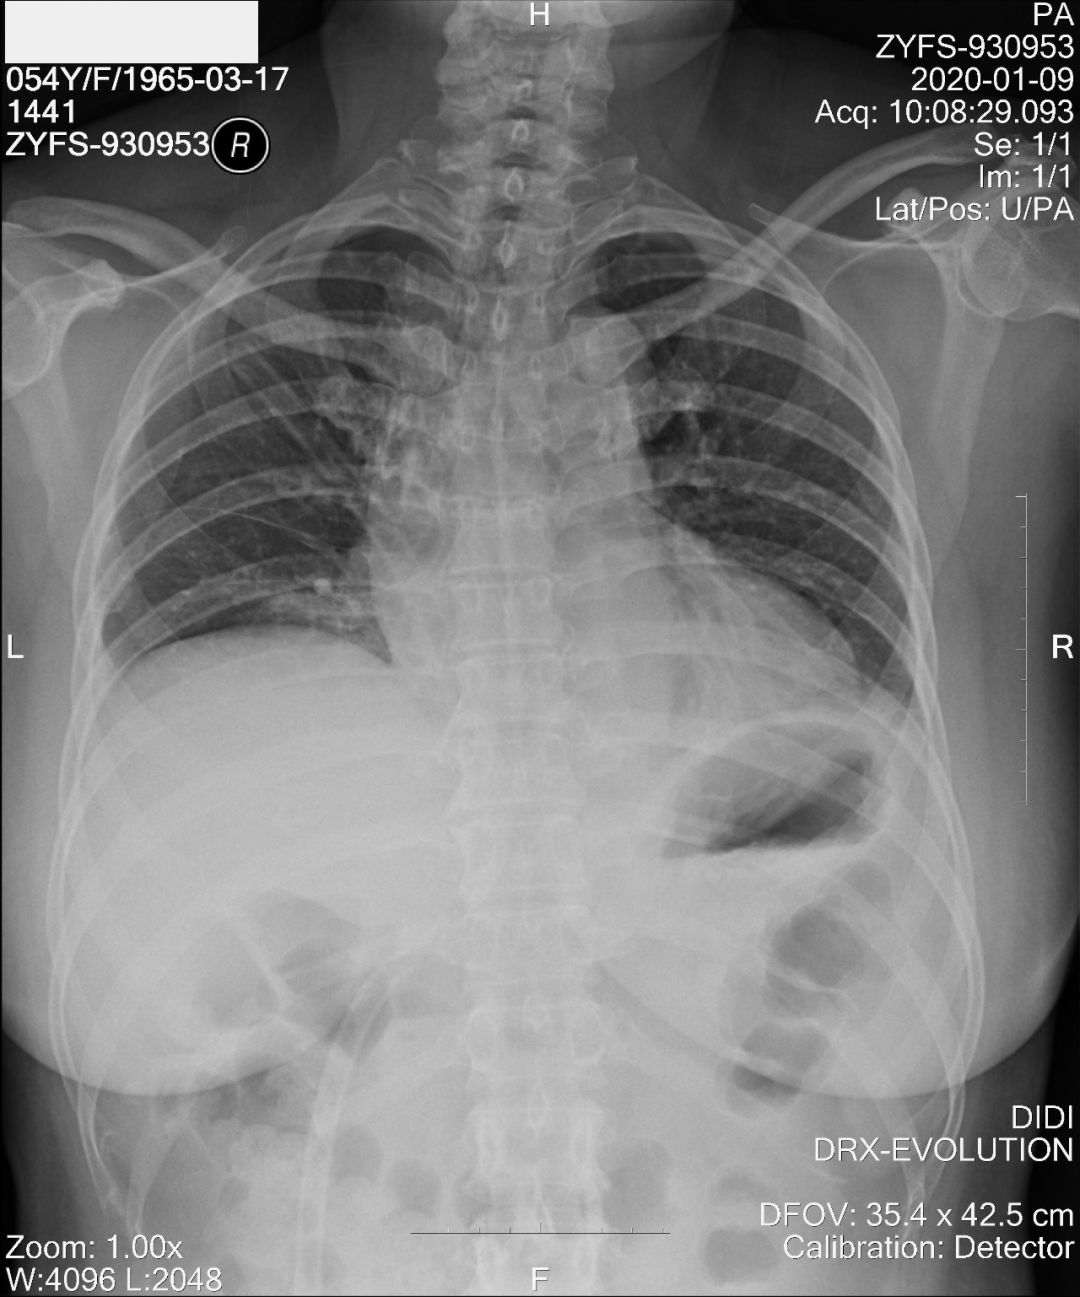

没想到我这么大岁数,切掉一个肺叶的十年后,再次做这么复杂的手术还这么顺利。 D大爷今年72岁,10年前曾行左肺上叶切除+淋巴结清扫术,手术标本病理为腺癌,术后给予了四次化疗。当时的胸部CT即可见右肺上叶小结节影,术后定期复查,病灶缓慢增大,一度略有缩小,此后再次逐渐增大。结合患者一直随访的影像学资料,杨如松院长考虑为右上肺新发恶性肿瘤。 2015年胸部CT 2020年胸部CT 虽然患者及其家属手术的意愿非常强烈,但此手术难度较高,原因在于: 1.患者年龄较高,手术风险大。 2.患者10 年前肺癌手术切除左边肺的一半,肺功能丧失较多。 3.病灶在右上肺的深部,切除有一定的难度。 为了保证患者术后的生活质量,我们不能够做肺的楔形切除这样的简单肺手术,而需要行肺段的切除。 EDDA重建提示病灶位置深 如果放在以前该患者就只能做做放化疗等保守治疗了。幸亏南京胸科医院目前引进了各种国内乃至国际上的先进技术。 如EDDA术前三D成像技术;只有单一3cm长切口的单孔胸腔镜技术;近红外荧光镜肺段、亚肺段精准定位技术等。 有了这些技术,杨如松院长心中有了底气。杨院长根据病人的情况设计手术方案,尽量减轻手术创伤,让接受第二次肺部复杂手术的高龄病人能够耐受,并且在术后能够顺利恢复。 根据术前EDDA三维重建,患者进行了单孔荧光胸腔镜S1a+2a切除术,术中先用ICG反染法确定段间面,再用膨胀萎陷法印证段间面,这保证了手术切除的精准性。 患者术中快速病理为贴壁型腺癌,这也印证了杨如松院长术前对患者肺结节良恶性的判断。 术后5天,D大爷非常顺利的出院了。出院前开心的窦大爷连声感谢杨如松院长:没想到我这么大岁数,切掉一个肺叶的十年后,再次做这么复杂的手术还这么顺利,谢谢、谢谢! 基本情况